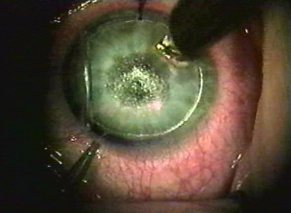

Traumatic cataracts may be observed even if the visual acuity is not compromised. Focal opacities of the peripheral lens causing glare and monocular diplopia may be managed with topical miotic agents. Emergent or urgent surgical removal of the lens may be needed in the case of pupillary block glaucoma caused by the lens dislocating into the anterior chamber, or in cases of lens particle induced or phacoantigenic glaucoma. [37] Surgical timing is also important to consider in a child, in whom amblyopia is a concern. Despite the timing of cataract extraction, the surgeon should be prepared to manage zonular dehiscence and anterior vitreous prolapse.

Intraocular Refractive Surgery

Refractive lens exchange and cataract surgery remove the crystalline lens and replace it with an IOL. Prior to the phacoemulsification era, extracapsular cataract (ECCE) surgery involved a large limbal incision or scleral tunnel. While ECCE incisions were historically as large as 10 mm in chord length, phacoemulsification cataract surgery employs a clear corneal incision (or narrow scleral tunnels), which typically ranges between 2.2 to 2.75 mm. Phakic IOLs (pIOL) are able to correct ametropia by lens insertion into 3 anatomical locations: anterior chamber iris fixated (Artisan/Verisyse), anterior chamber angle supported (Kelman Duet, Acrysof Cachet), or posterior chamber with no fixation (Implantable Collamer Lenses).[38][39] Incisions from these surgeries produce a potential area of weakness that may lead to wound dehiscence after trauma. Larger incisions from traditional ECCE are more likely to suffer dehiscence than smaller phacoemulsification or pIOL incisions.[40][41] Prior cataract surgery may stress the zonular support, and subsequent trauma may dislocate the implanted IOL. Ruptured ECCE wounds account for a significant proportion of all open globe injuries, and they are associated with a high possibility of retinal damage (e.g. choroidal hemorrhages and retinal detachment), often leading to a poor visual outcome. Dehiscence of the phacoemulsification wound is less common and is more frequently associated with a better visual prognosis. Other pathology related to trauma may involve IOL dislocation within the eye from an associated zonulopathy or capsular tear. The IOL may also be partially or completely expelled from globe through a weakened area (i.e. prior incisions).